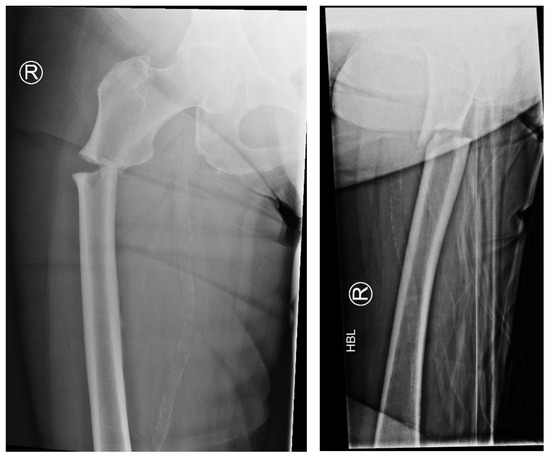

Management Concepts of Bisphosphonate-Related Atypical Femoral Fractures

Background/Objectives: Osteoporosis is an important health issue worldwide, and bisphosphonates are commonly prescribed for its treatment. However, certain complications can occur with long-term bisphosphonate therapy. The complication highlighted in...